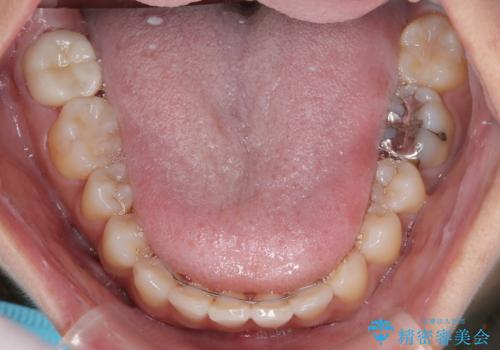

上顎の正中位置をほぼ保った状態で、綺麗に仕上げることができました。